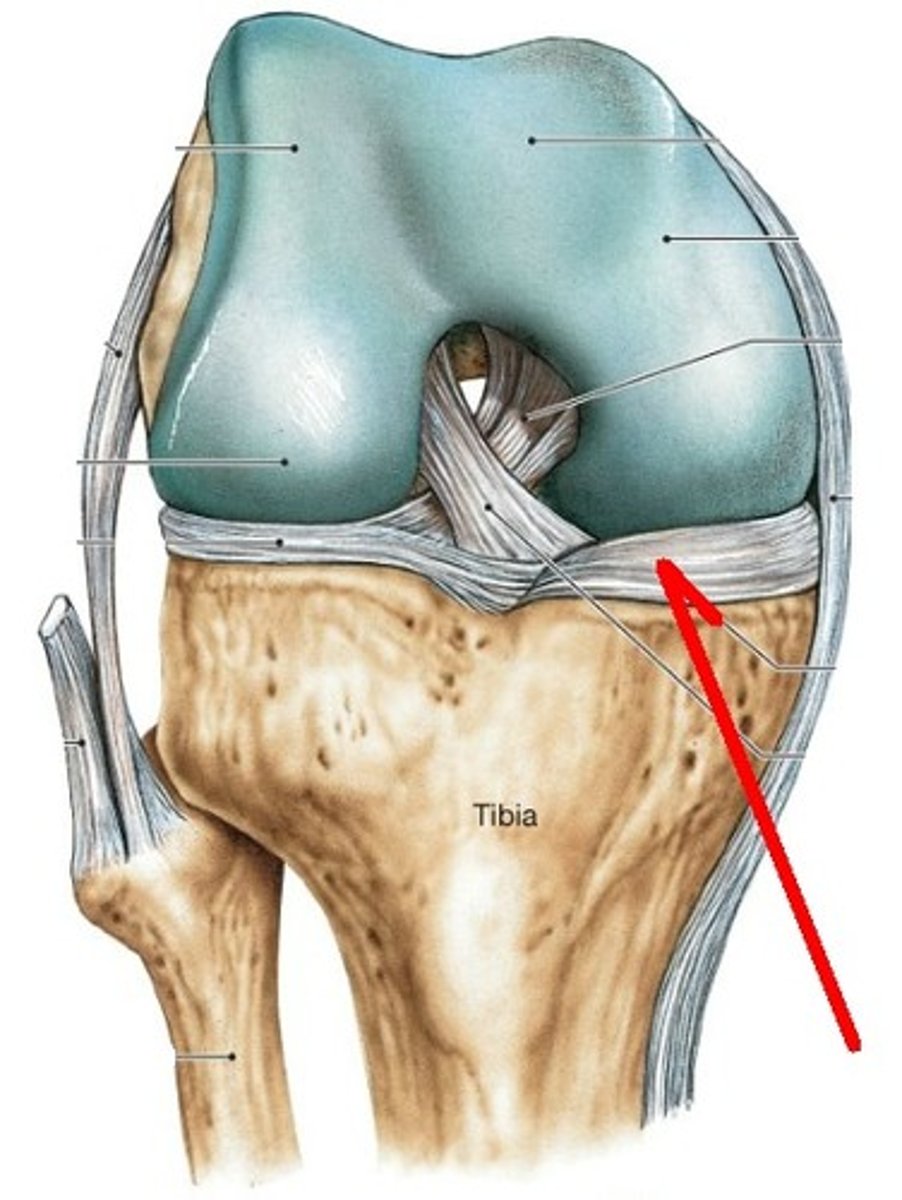

Tendon of Quadricepts

patella

Patellar Ligament

Fibular collateral ligament

Lateral Meniscus

Posterior Cruciate ligament

Tibial Collateral Ligament (MCL)

Anterior Cruciate Ligament (ACL)

Medial Meniscus

Unhappy trio

MCL, ACL, Medial meniscus